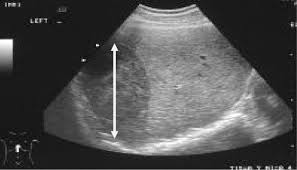

Heatomegaly

Hepatomegaly